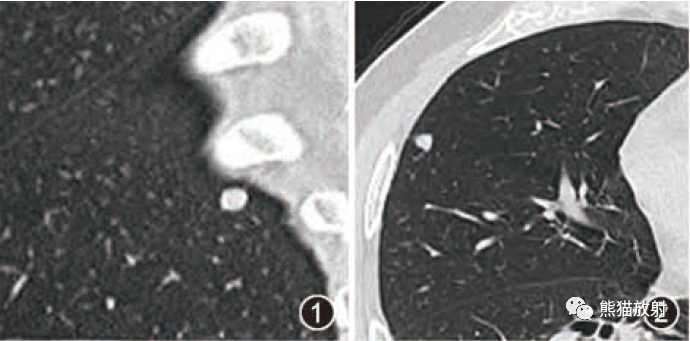

范围从小的微结节(<4mm)(图9)到较大的离散结节(通常达1cm),以及较大的结节或肿块(图10)。后者常被描述为具有不规则或锐利边缘,通常包含支气管充气征(图11)。结节可以单发或多发,通常为实性结节或部分实性结节(图12)。虽然PET扫描对这些病变的评估显示标准化摄取值轻微升高,但结果是非特异性的,临床价值有限(图13、14)。不常见的OP类型为小结节型,包括弥漫性小叶中心型模糊结节(如在非纤维性过敏性肺炎[HP]病例中可见)和树芽征,提示细支气管感染和/或炎症。

图9 微小结节。同一患者的高分辨率CT轴位扫描切面(A)和最大密度投影图像(B)。CT扫描图像显示双肺多发小实性结节,提示可能的恶性肿瘤或感染。CT扫描引导下的针吸活检结果与机化性肺炎的诊断一致。